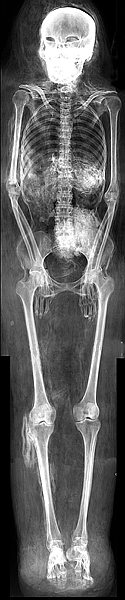

Mumie einer Frau

Röntgenaufnahme

3. Zwischenzeit, 11.-10. Jh. v. Chr.

Herkunft unbekannt

Menschenmumie, Leinwand L. 156,6 cm, Br. 38 cm, T. 26 cm

Kunsthistorisches Museum Wien, Ägyptisch-Orientalische Sammlung